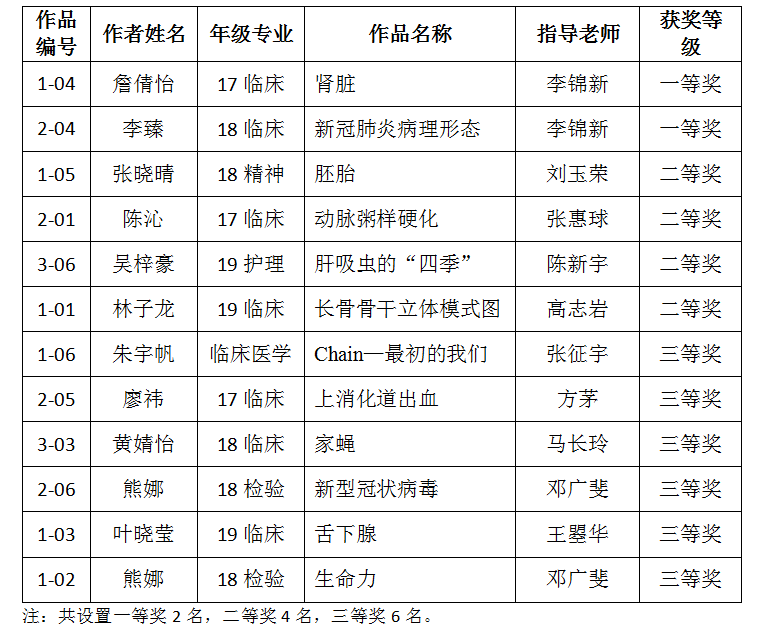

一等奖作品(1):肾脏 作者:17级临床医学 詹倩怡